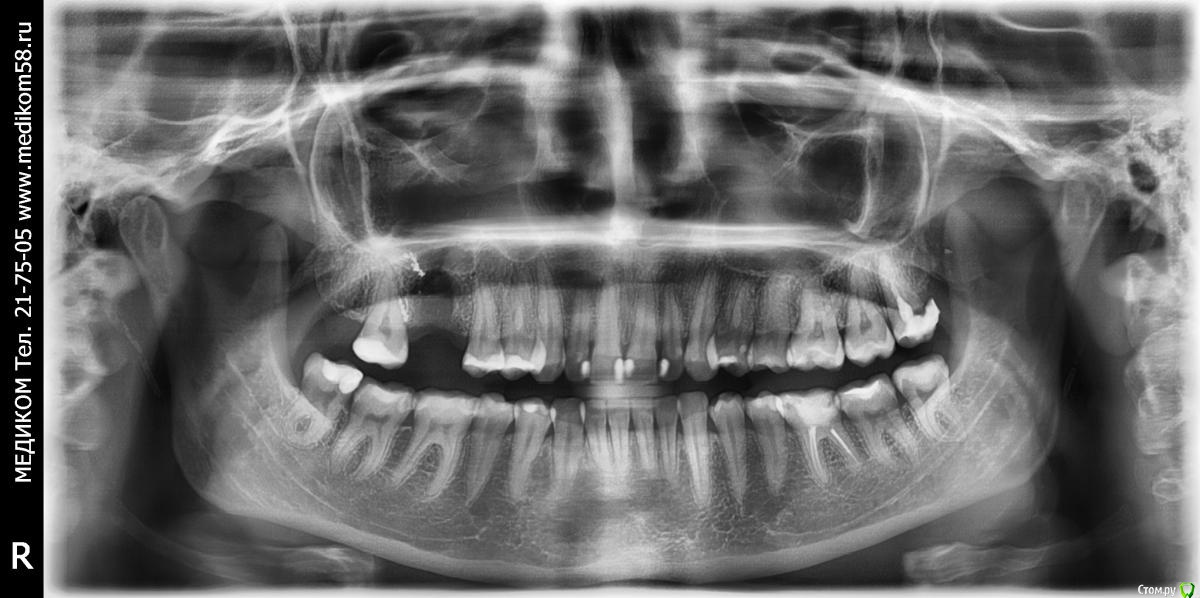

Таран Милана Опубликовано 22 июля, 2018 Автор Поделиться Опубликовано 22 июля, 2018 Немного ноет щека, где зуб выдрали, мне писали что врач произвел нетчательный кюретаж в лунке, остался пломбировочный материал. А вообще мне хотелось бы знать о зубах пораженных кариесом. Ссылка на комментарий

red_butler Опубликовано 23 июля, 2018 Поделиться Опубликовано 23 июля, 2018 1. 2.8 3.8 4.8 (зубы мудрости) удалять2. 3.6 протезировать 1 Ссылка на комментарий

red_butler Опубликовано 23 июля, 2018 Поделиться Опубликовано 23 июля, 2018 Извините, а можно немного доходчивее? это как? Зачем все зубы мудрости удалять? на верху слева, разрушен и воспаление. Внизу справа зуб лишен антагониста и выдвигается. Слева большая пломба и скоро лишится антагониста. Удаляйте если не хотите проблем с седьмыми зубами 1 Ссылка на комментарий